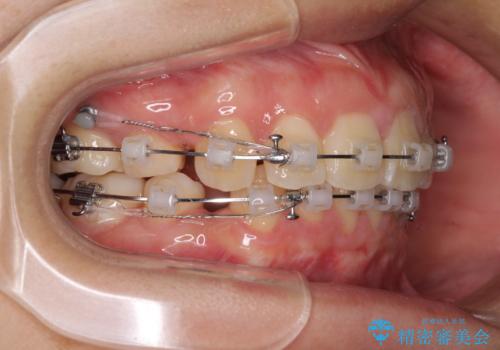

- クリアブラケット

- 2年5ヶ月

- 10-30回

- 上下前歯を部分矯正したところ出っ歯になってしまったとのことで来院された患者様です。

上下左右第一小臼歯4本を抜歯して、積極的に口元を引っ込めるよう、ワイヤー装置にて矯正治療を行うこととしました。